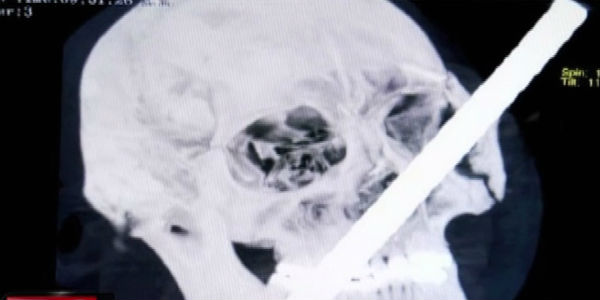

El obrero de construcción Anderson Chavarría Sinche se recupera luego de ser operado exitosamente en Clínica Internacional. Fierro le atravesó la cabeza cuando ayudaba en una obra en Tarma.

De emergencia fue trasladado a Lima el obrero que terminó con un fierro incrustado en el rostro. Hoy fue operado con éxito en una clínica de la capital.